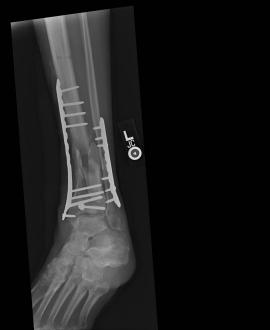

Post-skin graft & bone infuse surgery X-Rays of the left & right ankle

These x-rays were taken four weeks after surgery where grafts of skin were used to cover the open wound on Liam's left ankle. Dr. Gottlieb

infused bone material into the tibia gap of the left ankle. The 3 cm fragment in the left ankle does not appear to have fused or to be

obstructing normal movement so no immediate plans exist to modify the remaining bone fragments. Following these x-rays it is the plan to

remove the right ankle screw that was misplaced by Dr. Keller.